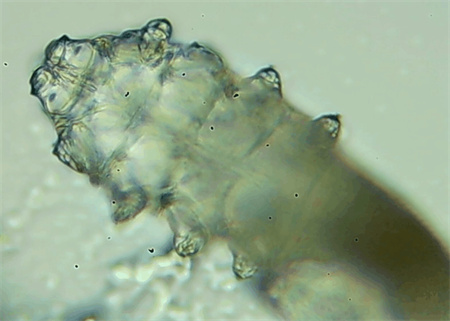

把玻片放到顯微鏡下觀察,通過電腦實時傳送的畫面,可以查看到這些拔下來的睫毛上是否有螨蟲。

結(jié)果,有6個人拔下來的睫毛上都發(fā)現(xiàn)了螨蟲。

這種螨蟲叫做蠕形螨,他們通常呈乳白色、半透明的細長狀,擁有四對腳。它們跟被子上的塵螨可不是同一種。